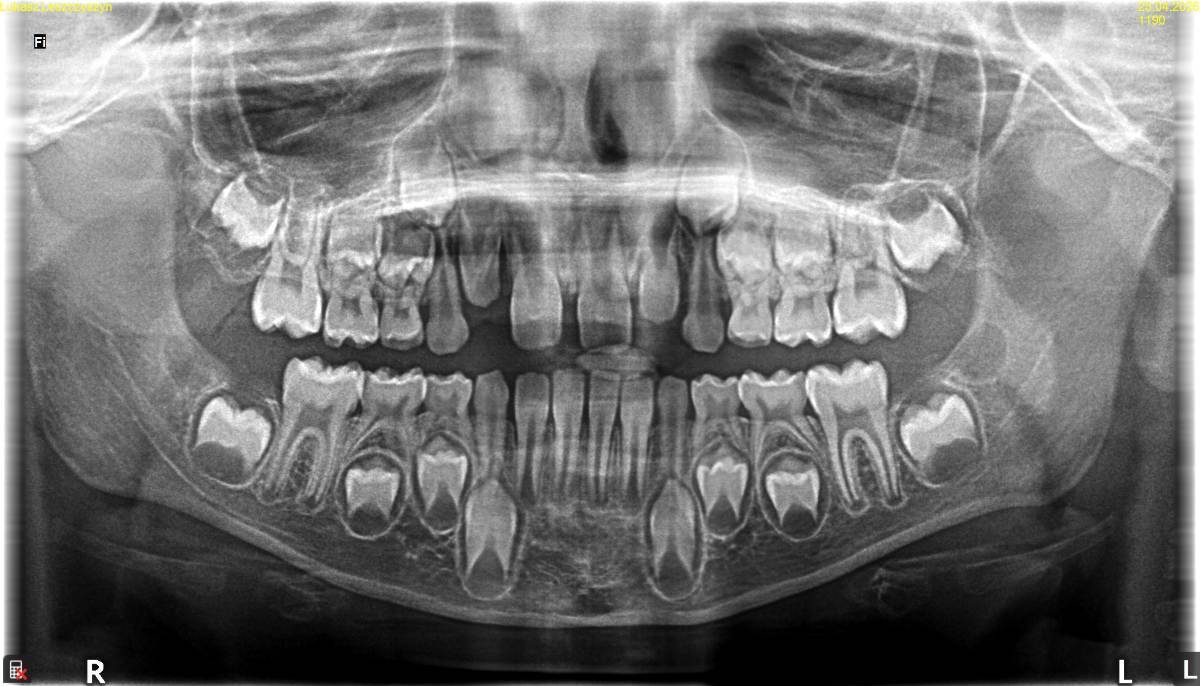

Ребенок 7 лет. Визуально - передний зуб выступает немного вперед. Между передними зубами пробел. Хотелось бы чтобы пробела не было.

Вот были у ортодонта. Все, что он сказал - записаться к нему на коррекцию 3х уздечек. Лазером. Он видит в этом главную проблему. И работать с логопедом. Но с логопедом работаем.  Еще что-то вспоминал про то, что у ребенка плохо развивается челюсть. Это как-то видно по рентгене?

Я читал, что если такие дела с передними зубами, то нужно ставить пластинку. Да? Возможно, после этого он хотел делать пластинку?

Спасибо за советы и ответы. А как двигаться с расстоянием между зубами и тем, что один передний зубик немного идет вперед? Пойти к другому ортодонту, чтобы назначил пластинку? Или каждый день давать грызть морковь, чтобы зубы сами стали на место? Или когда вылезут зубы по бокам, оно должно придти в норму само?

Кстати, вот рентген черепа старшего сына.